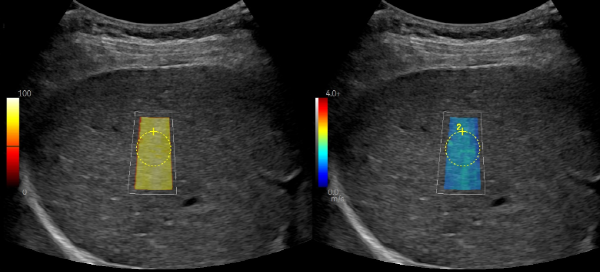

°£¼¶À¯È­ ½ºÄµ°Ë»ç

º¹ºÎÃÊÀ½ÆÄ¿Í Ç÷¾×°Ë»ç¸¸À¸·Î´Â ¾Ë±â ¾î·Á¿î ÀáÀçÀû °£º´º¯Áõ ȯÀÚ¸¦ Á¶±â¿¡ ¹ß°ßÇÒ ¼ö ÀÖ½À´Ï´Ù.

°£°æº¯ÁõÀº Ȳ´Þ, º¹¼ö, ÃâÇ÷ µîÀ» À¯¹ßÇÒ ¼ö ÀÖ°í °£¾ÏÀ¸·Î ÁøÇàÇÒ À§Ç輺À» °®°í ÀÖ´Â ÁúȯÀÔ´Ï´Ù. ±âÁ¸¿¡´Â Á¶±â °£°æº¯Áõ ȯÀÚ¸¦ Áø´ÜÇϱâ À§ÇØ °£ Á¶Á÷ÀÇ ÀϺθ¦ ¶¼¾î³»´Â Á¶Á÷°Ë»ç·Î °£¼¶À¯È­ Á¤µµ¸¦ ÆÄ¾ÇÇØ¾ß Çß½À´Ï´Ù. °£¼¶À¯È­ ½ºÄµ°Ë»ç´Â Á¶Á÷°Ë»ç¸¦ ´ëüÇÒ ¼ö ÀÖ´Â ¾ÈÀüÇÏ°í ºñħ½ÀÀûÀÎ ¹æ¹ýÀ¸·Î, º¹ºÎÃÊÀ½ÆÄ¿Í Ç÷¾×°Ë»ç¸¸À¸·Î´Â ¾Ë±â ¾î·Á¿î ÀáÀçÀû °£°æº¯Áõ ȯÀÚ¸¦ Á¶±â¿¡ ¹ß°ßÇÒ ¼ö ÀÖ½À´Ï´Ù. º»¿øÀº ÃÖ½ÅÀÇ ÃÊÀ½ÆÄ Àåºñ·Î °¡Àå Á¤È®ÇÑ ¹æ¹ýÀÇ °£¼¶À¯È­ °Ë»ç(2D-Shear wave elastography)¸¦ ½ÃÇàÇϰí ÀÖ½À´Ï´Ù.